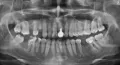

Зуб однозначно удаляется по причине обширного воспалительного процесса.

Также зубы 46, 45 в консольной конструкции имеют воспаление на верхушках зубов.